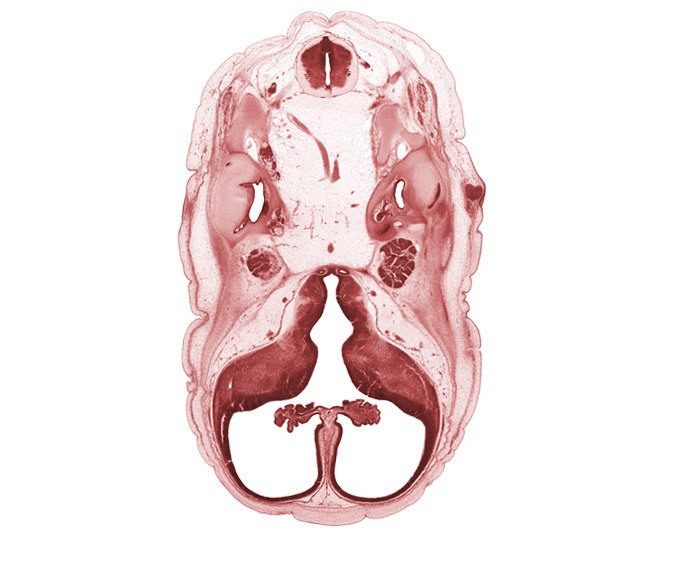

Carnegie Embryo #4090 | Location: 8-9

Keywords: C-1 spinal nerve, anterior semicircular duct, artifact separation(s), basilar artery, choroid plexus, facial nerve (CN VII), hypothalamic sulcus, hypothalamus, interventricular foramen, junction of basilar artery and vertebral arteries, lateral semicircular duct, lateral ventricle, lateral ventricular eminence (telencephalon), medial ventricular eminence (diencephalon), motor root of trigeminal nerve (CN V), neurohypophysis, osteogenic layer, posterior semicircular duct, saccule(s), sigmoid sinus, spinal accessory nerve (CN XI), subarachnoid space, third ventricle, tuberal part of adenohypophysis, utricle, vertebral artery

Source: The Virtual Human Embryo.